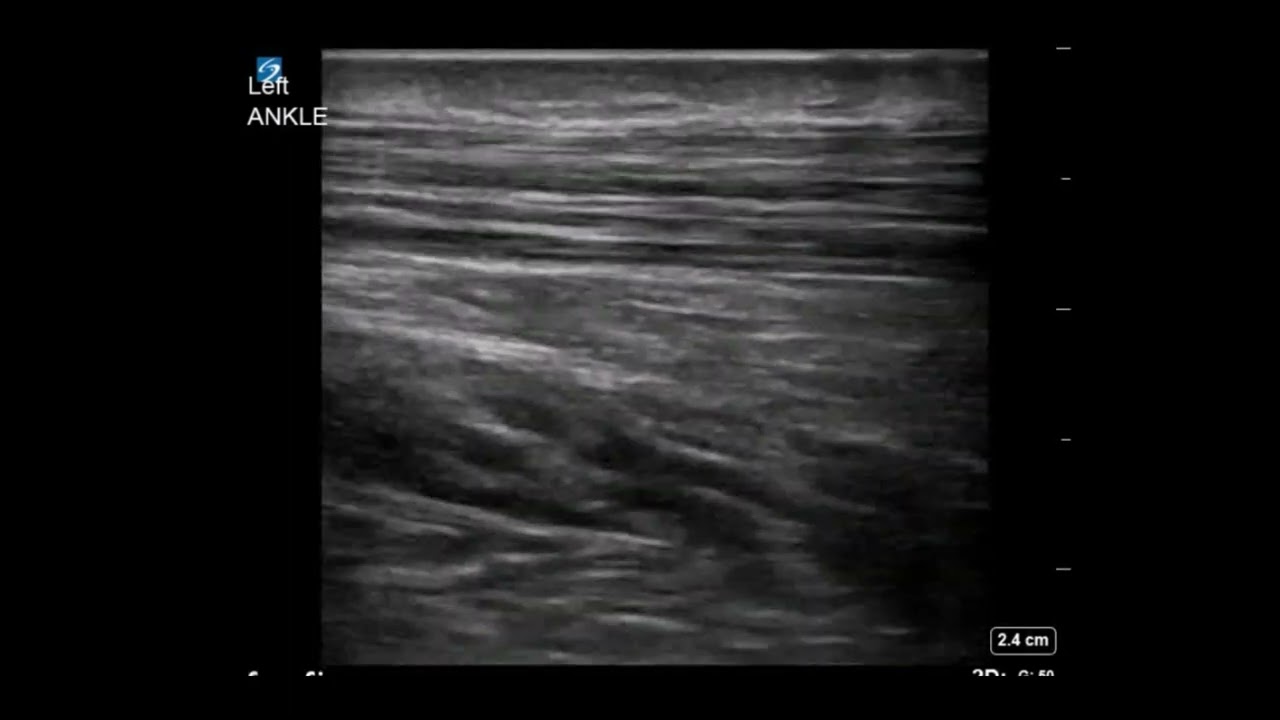

From www.youtube.com

Ankle US Achilles Tendonitis With Enthesophyte YouTube Achilles Enthesophyte Definition Treatments can include medications, physical. It is characterised by inflammation, degeneration, or damage at this point. The term achilles tendinopathy refers to tendinitis (acute inflammation) and tendinosis (chronic inflammation). Achilles tendon enthesopathy is pain at the insertion of the achilles tendon at the posterosuperior aspect of the calcaneus. Inflammation can begin suddenly after an injury or more gradually. L’enthésopathie du. Achilles Enthesophyte Definition.